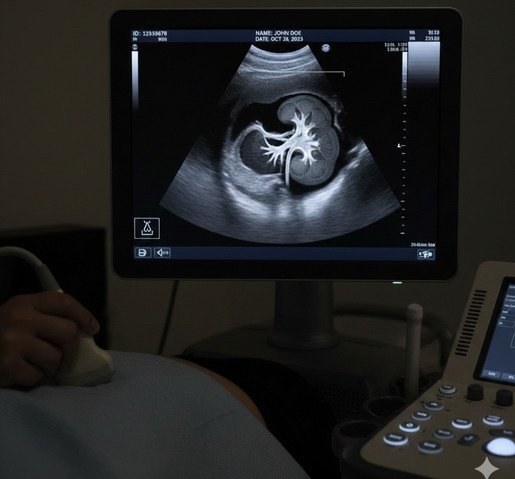

Ecografía Renal

La ecografía renal es un estudio no invasivo que permite evaluar los riñones, analizando su tamaño, forma, estructura y la presencia de posibles alteraciones como litiasis, quistes, dilataciones o cambios parenquimatosos. Es una herramienta fundamental para el diagnóstico y seguimiento de diversas patologías del sistema urinario.

Se trata de un estudio seguro, indoloro y de rápida realización, indicado tanto en controles de rutina como ante síntomas urinarios o enfermedades renales conocidas.

En LUMA, la ecografía renal es realizada por profesionales especialistas en diagnóstico por imágenes, utilizando equipos de última generación y alta definición, que permiten obtener imágenes claras y precisas para un diagnóstico confiable.